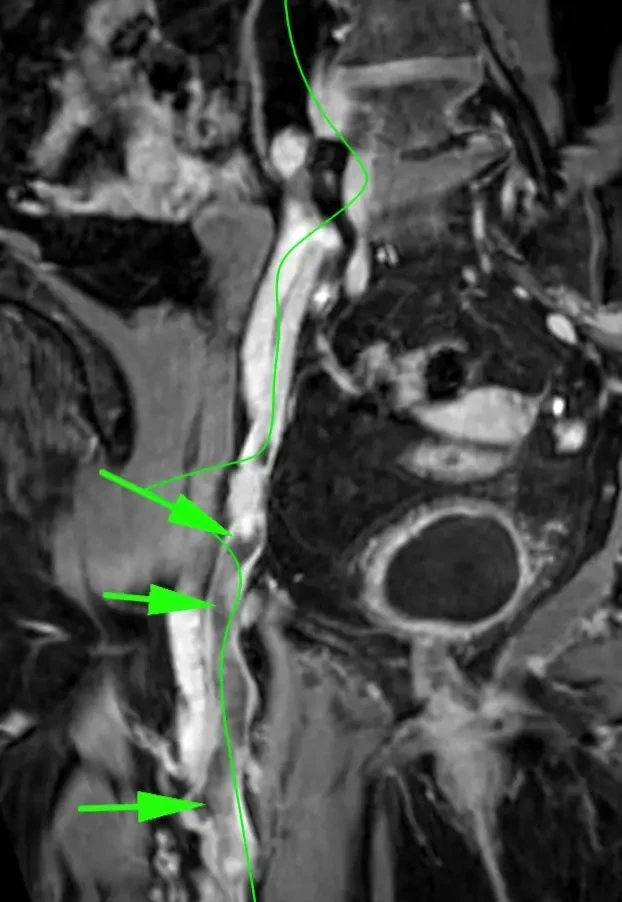

Менингиомы иногда не ходят одни. А по две, три и больше. Самая крупная слева в ЗЧЯ - хорошо видно место, из которого она растет: фокальные утолщения кости по краям и плоское основание опухоли (стрелки).